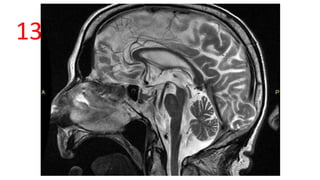

HUMMING BIRD SIGN / PENGUIN SIGN

• Midsagittal MRI – atrophy of midbrain tegmentum with relatively preserved pons.

• Seen in Progressive Supranuclear palsy (PSP)

MIDBRAIN

TEGMENTUM=BILL

ROSTRAL

MIDBRAIN=HEAD

PONS = BODY

CEREBELLUM = WING